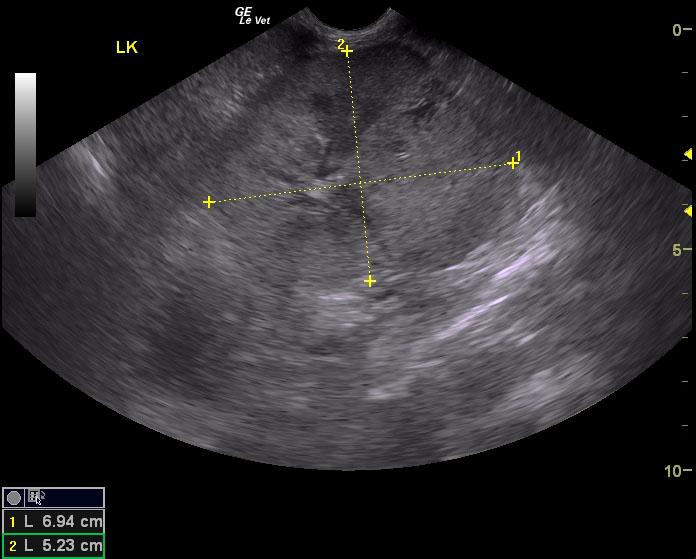

A 12½-year-old neutered male DSH cat with a history of hypertension controlled with amlodipine was presented for evaluation of PU/PD and weight loss. On physical examination, a cranial abdominal mass (suspected kidney) and moderate muscle atrophy was present. Abnormalities on CBC and serum biochemistry included neutrophilia and azotemia. Prior urine analysis had shown proteinuria with a SG of 1.028.

A 12½-year-old neutered male DSH cat with a history of hypertension controlled with amlodipine was presented for evaluation of PU/PD and weight loss. On physical examination, a cranial abdominal mass (suspected kidney) and moderate muscle atrophy was present. Abnormalities on CBC and serum biochemistry included neutrophilia and azotemia. Prior urine analysis had shown proteinuria with a SG of 1.028.